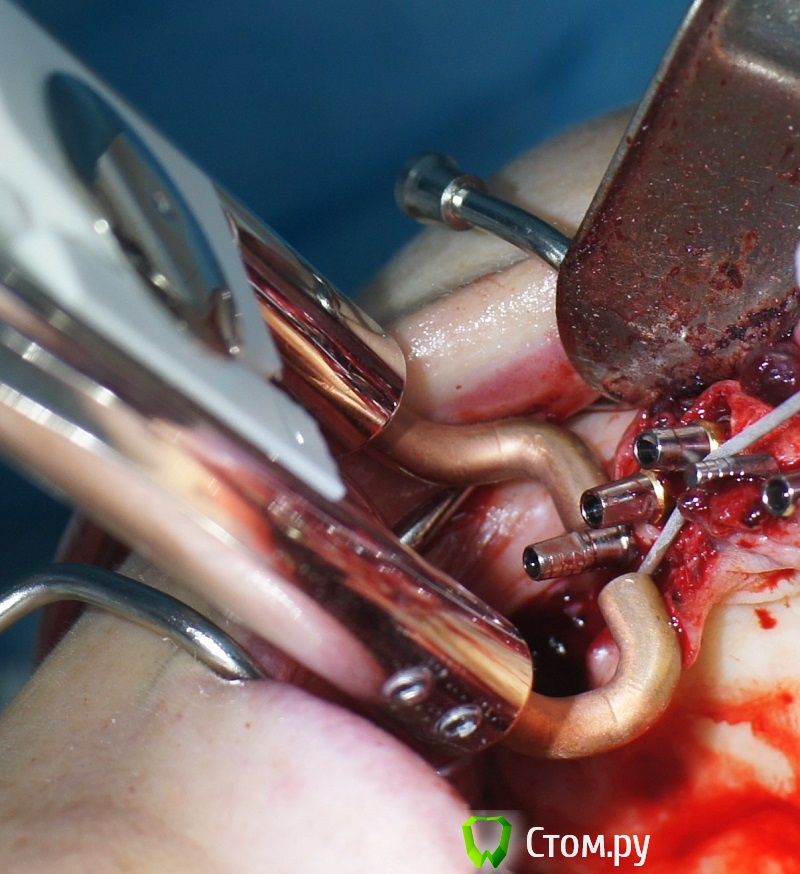

rin3225 Опубликовано 8 октября, 2014 Поделиться Опубликовано 8 октября, 2014 У пациента было желание сделать красивые зубы и улыбку!Проблема заключалась в массивной верхней челюсти , глубоком перекрытии и пациент не мог уйти без зубов! Отлив модели и выставив в центральную окклюзию было понятно, что без удаления всех зубов и поднятия прикуса с данной проблемой вопрос не решится. Обговорив все нюансы с пациентом,и получив согласие, было запланировано. заранее изготовлены акриловые протезы, предложено удаление всех зубов с одномоментной установкой имплантатов, внутриротавая сварка для первичной стабильности имплантатов и немедленная нагрузка 16 Ссылка на комментарий

rin3225 Опубликовано 8 октября, 2014 Автор Поделиться Опубликовано 8 октября, 2014 если не сложно-показания к внутриротовой сварке?какая была первичная стабилизация имплантатов?эти поперечные балки в поддесневой зоне,не будет ли здесь проблем?Спасибо.Показания как я писал для первичной стабильности имплантатов, немедленной нагрузки,и распределение нагрузки. По поводу первичной фиксации в разных участках была разная, кость 3-4 го типа от 20 до 30 То, что балки под десной, какие проблемы должны быть? Ссылка на комментарий

rin3225 Опубликовано 8 октября, 2014 Автор Поделиться Опубликовано 8 октября, 2014 Зачем так много имплантатов?Почему проволока приварена в поддесневом пространстве?Каким образом крепятся протезы? Ведь фиксация должна быть винтовая, а каркасс должен располагаться внутри протеза. Проволку можно преварить как под десной так и над десной, это не каркас протеза, протезы сьемные для соблюдения гигиены.В дольнейшем кострукция будет поменена на несьемные 1 Ссылка на комментарий